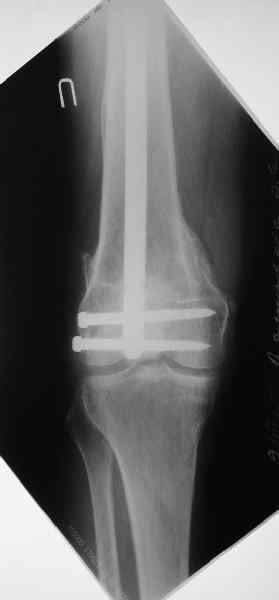

Чтобы больной не смог сгибать колено, выстоять в сустав железо должно побольше значительно, чем на 1 мм. В приложении снимок с выстоянием ммм на 3, видна и функция колена. Хотя клиника импинджмента была, но даже не на один восклицательный знак. После удаления стержня проблемы и вовсе рассосались.